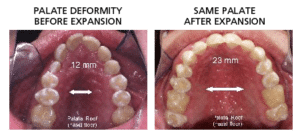

This is the big one and most often overlooked…Poor Facial Development and Failed Orthodontics are the leading causes of TMJ Pain and Sleep Apnea. Small Mouths and airways cause poor sleep. Few things are more important to a Kids overall health than proper Mouth and Facial Development.

Normal Palatal Size and Shape

Our main concern – We do not want your child to end up with a small mouth or small face or in general any facial under development. Facial, Jaw and Profile Under Development Causes:

- Tooth Crowding and Expensive Orthodontic Problems

Small and Deep Palate